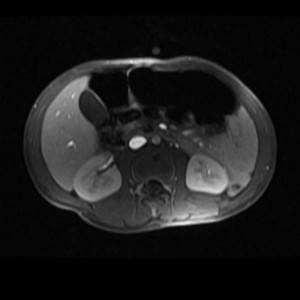

- Магнитно-резонансная томография брюшной полости

- Разрабатывая план будущей операции, специалист назначает целый комплекс исследований: компьютерную томографию, ангиографию, сканирование тканей печени (радиоизотопное), магнитно-резонансную томографию. Данные этих исследований помогают уточнить объем требующегося хирургического вмешательства.

Специфических методов диагностики гепатобластомы не существует. Общий осмотр и пальпация живота позволяют определить наличие образования в правом подреберье. УЗИ печени и брюшной полости при гепатобластоме выявляет расположение опухоли, степень ее распространения, количество узлов, поражение печеночных сосудов и нижней полой вены. КТ и МРТ, радиоизотопное сканирование печени и ангиография помогают при определении стадии заболевания и планировании объема операции.